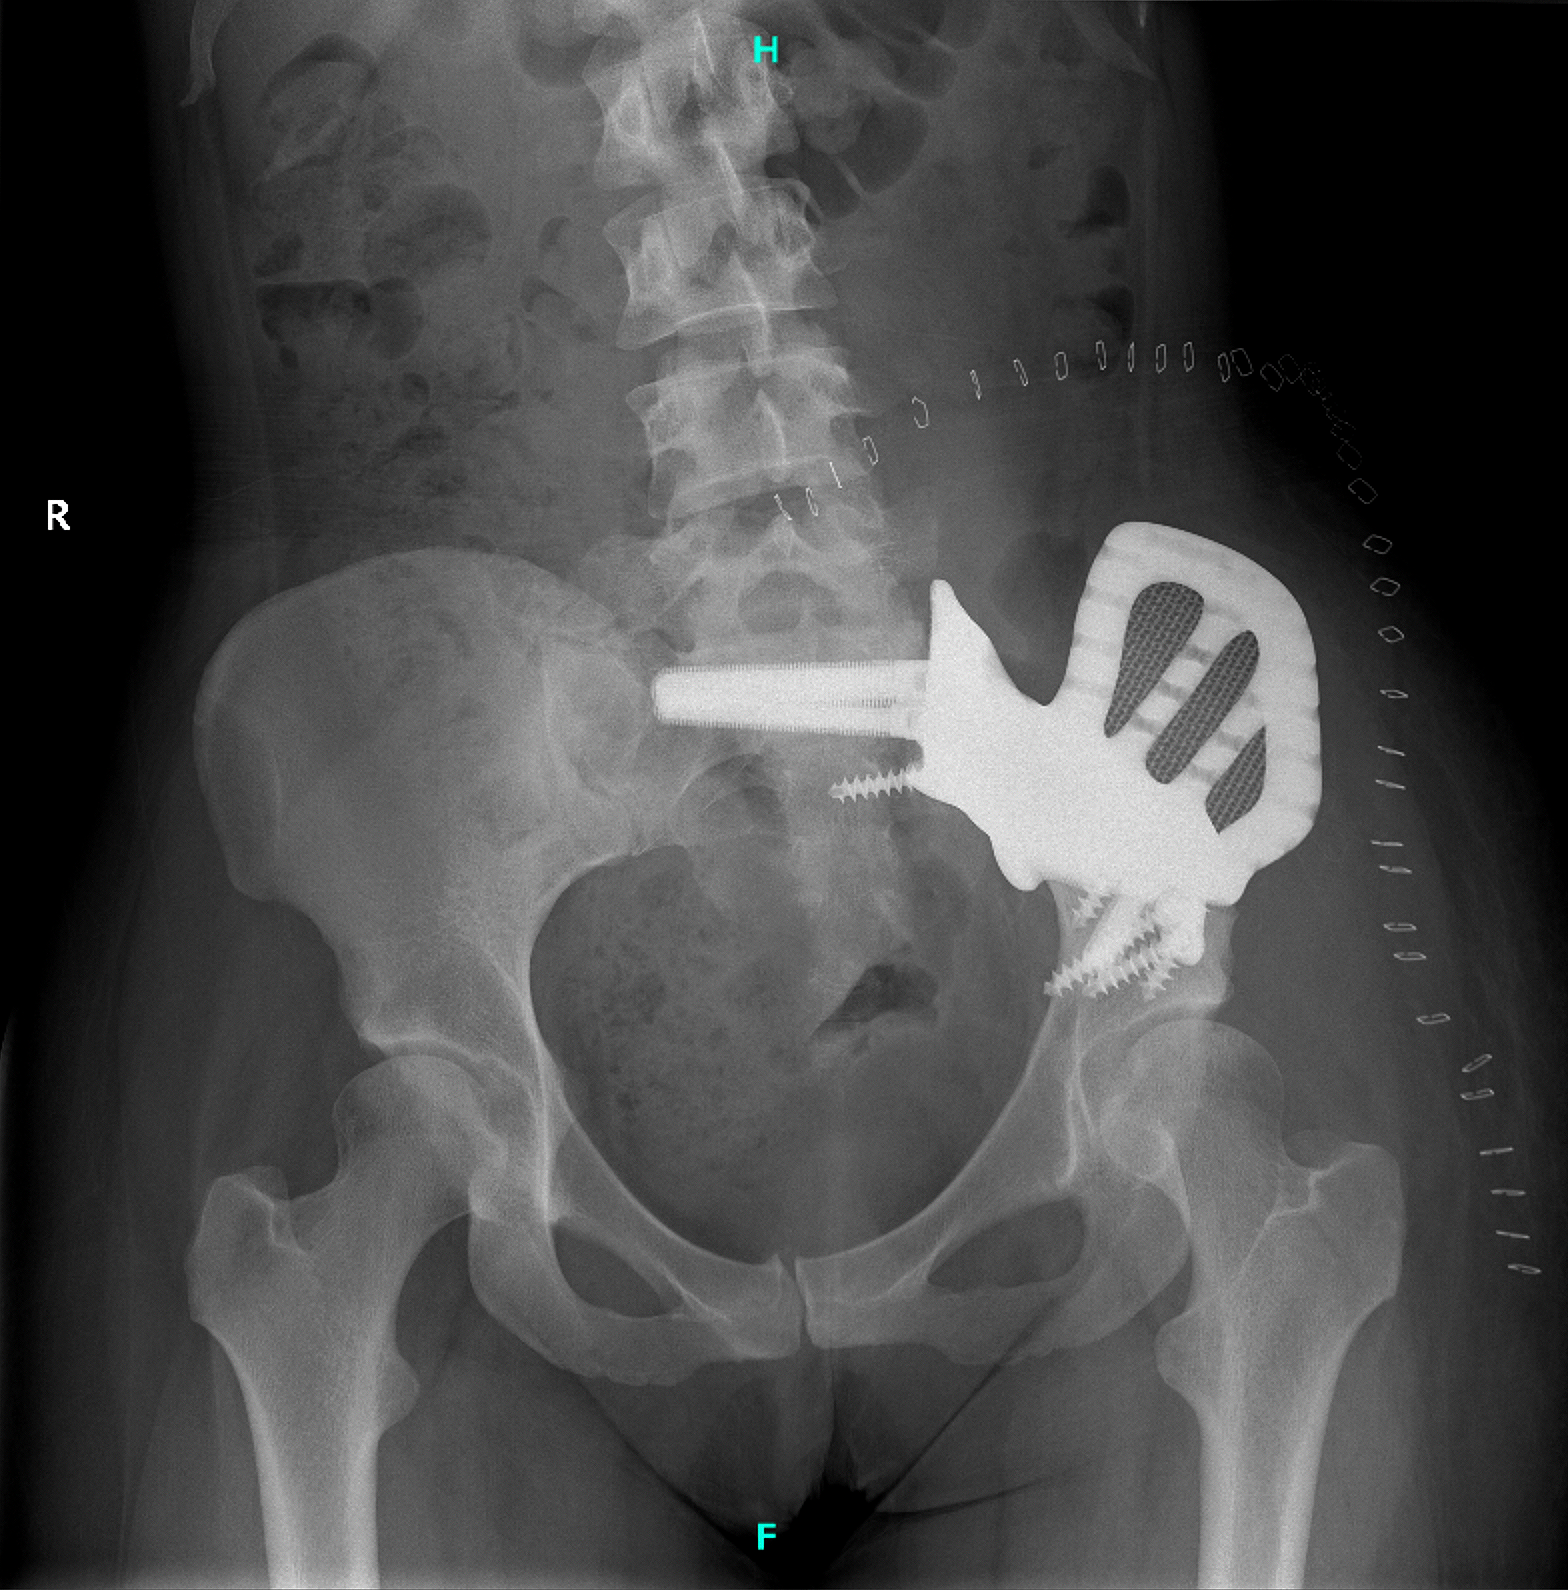

The surgery involved a wide resection of the iliac wing and a partial sacrectomy. These procedures were performed using patient-specific saw guides.

A custom sacroiliac joint replacement was then implanted with secure anchorage in the ilium and sacrum.

The patient’s recovery was uneventful. She was discharged after three weeks without any complications.

She was then initiated on partial weight-bearing, followed by structured rehabilitation. The implant provided

stable fixation, restored pelvic continuity, and preserved the native hip joint.

Figure 6: Postoperative anteroposterior pelvic X-ray confirming the correct positioning and fixation of the custom-made implant.